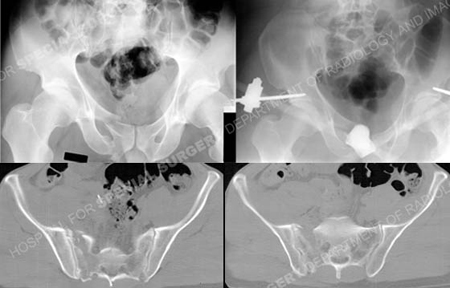

Anteroposterior injury pelvic radiograph (top left image) revealing a left-sided pelvic fracture including a sacral fracture and superior and inferior pubic rami fractures, anteroposterior pelvic radiograph following initial closed reduction and placement of anterior pelvic external fixation (top right image), and CT scan images further illustrating the sacral fracture pattern.